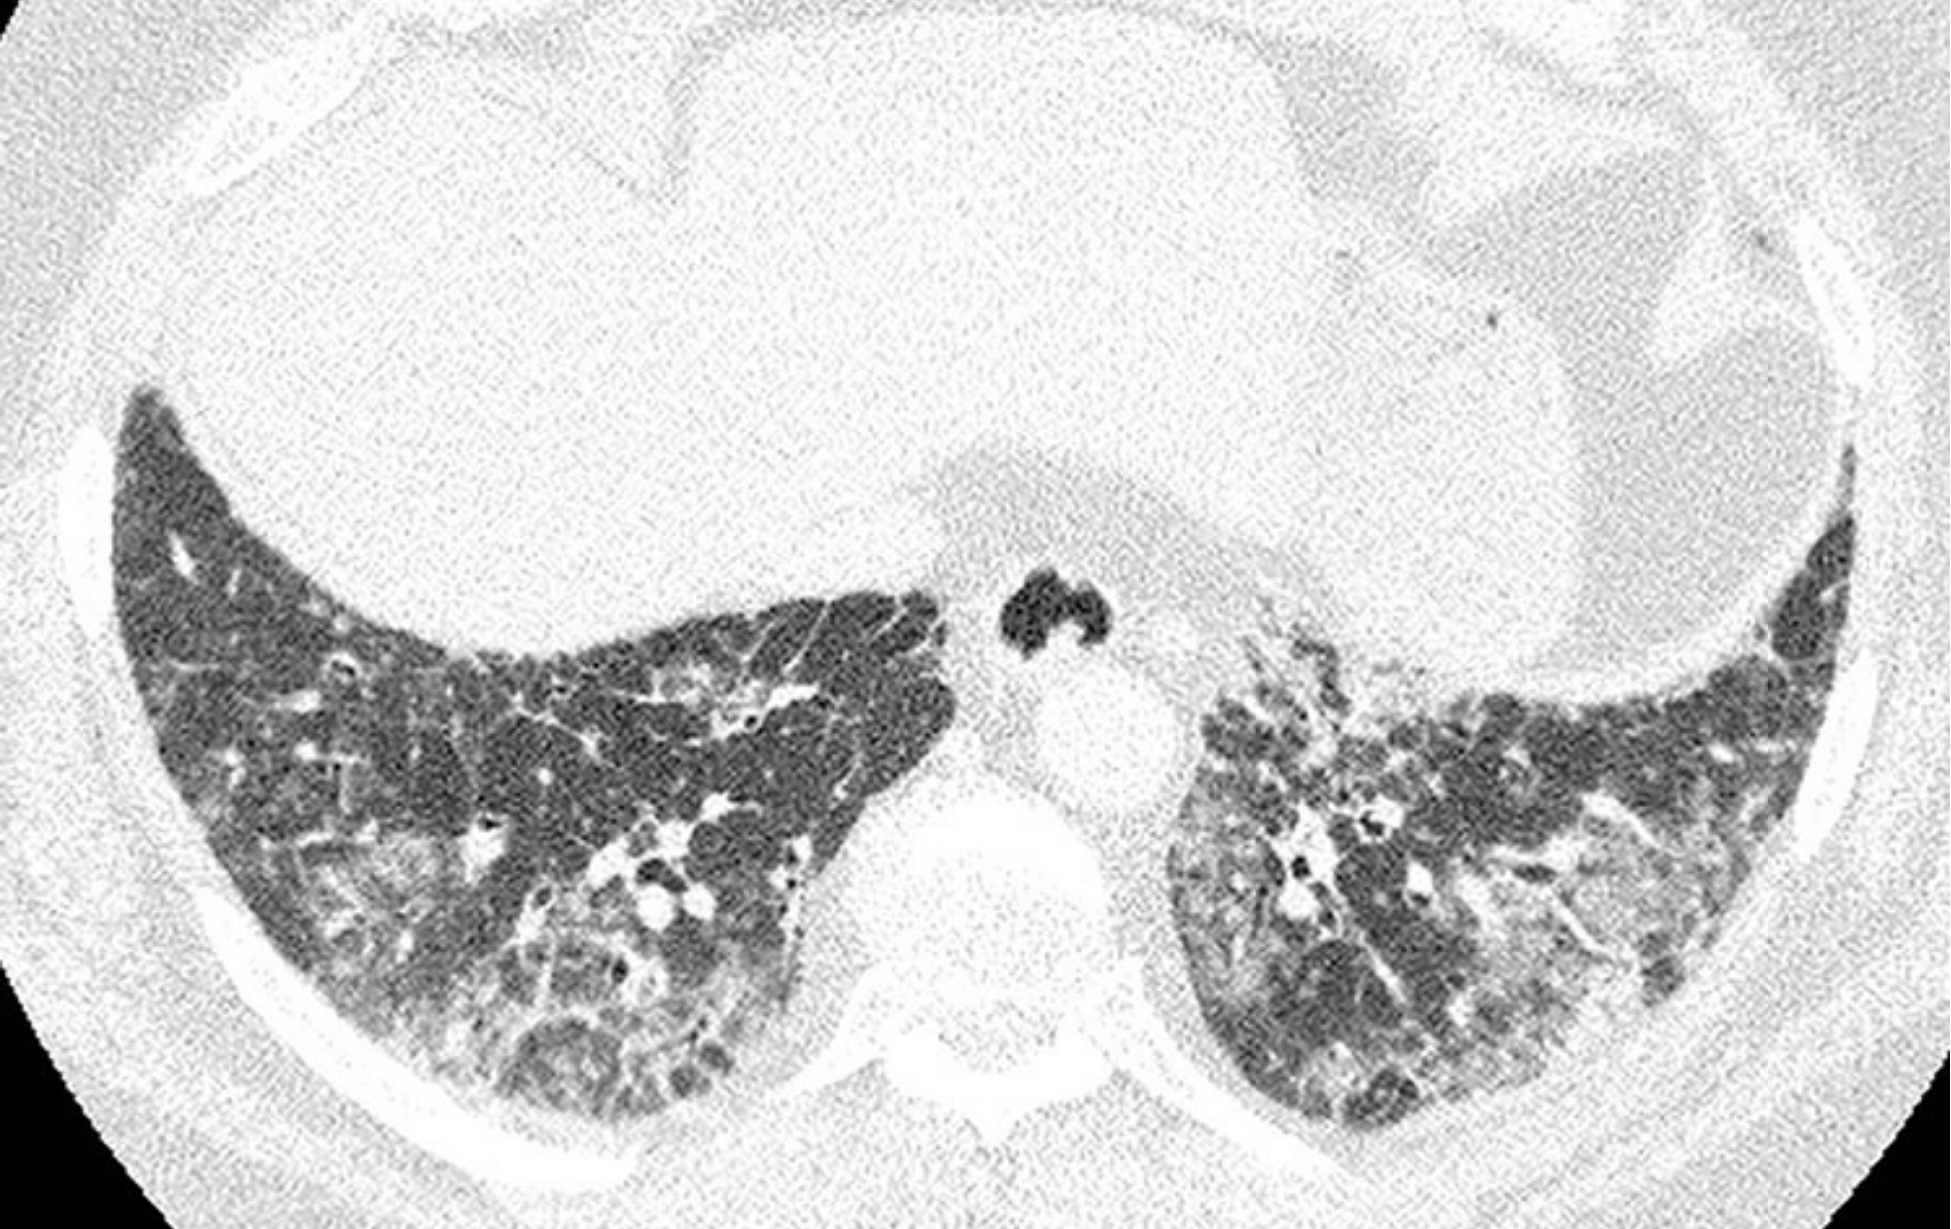

特发性肺间质纤维化(IPF),不典型分布。

该IPF患者经肺活检证实为普通型间质性肺炎(UIP),其不典型表现为纤维化不以胸膜下分布为主而是明显累及肺中央区(A)。

另外,肋膈角相对不受累(B)。IPF的不典型征象不少见。从HRCT表现上看,本例可能被认为与UIP “相悖”。

88af05edaac2a8a6b3a47e46d1ed6fd6.jpg特发性肺间质纤维化(IPF),不典型分布。